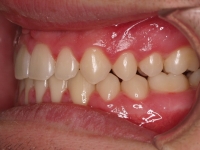

El paciente E.A. acude a nuestra consulta por diastema inferior y ausencia de contactos en los sectores laterales.

Chica de 17 años tratada en 1 año con stripping en los dientes inferiores